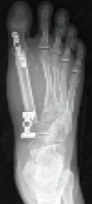

手术当天,麻醉手术部阳婷婷医生凭借丰富临床经验,顺利完成椎管内麻醉。在韩学哲与边卫国教授的指导下,杨卫周与刘俭涛医生精准切除受累的第一跖骨与内侧楔骨,并与整形外科何林医生顺利切取长约11厘米的小腿处带血管蒂腓骨,再通过“移花接木”式技术,将其移植至脚趾缺损部位。通过精细的显微外科技术,团队成功吻合足背血管,恢复移植骨块血运。在多科室通力协作下,手术圆满完成。